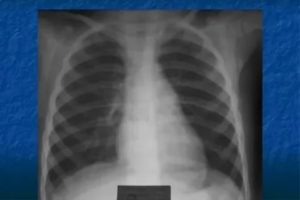

Диагностика грудной клетки в двух проекциях проводится в прямом и боковом снимке. Прямую проекцию по-иному называют переднезадней — название основано на том, как проходят рентгеновские лучи через грудную полость пациента. При обследовании бокового положения нет разницы, в правую или в левую сторону к экрану ставят пациента.

Изображение в боковой проекции является второстепенным — помогает лучше рассмотреть те органы, которые были ближе расположены к экрану. Прицельная боковая проекция чрезвычайно важна для определения объёмов пневмонии и локализации очага воспаления, а также для определения расположения новообразований в лёгких.